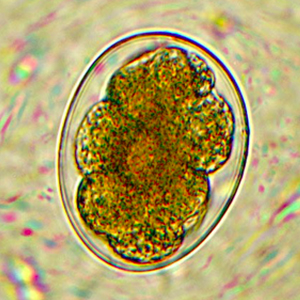

Les œufs de Necator americanus possèdent les caractéristiques morphologiques des œufs d’ankylostomes. Ils sont indifférenciables des œufs d’Ancylostoma à l’examen coproscopique (Strait et al., 2012).

Il comprend les nématodes du genre Ancylostoma et, de façon plus générale, tout œuf de strongle non embryonné.